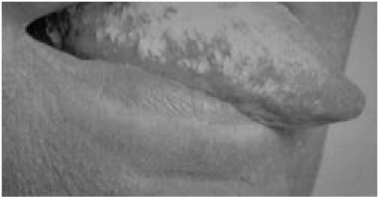

1.4.1.5.1一、症状及体征